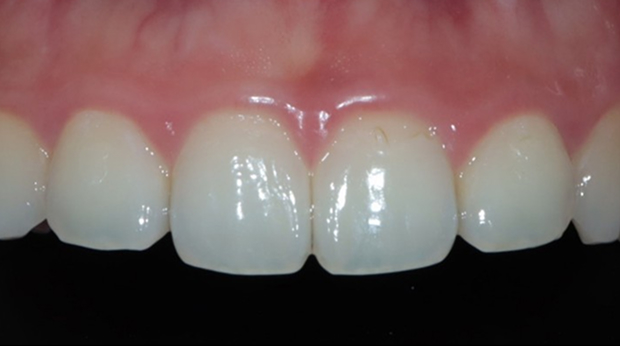

라미네이트